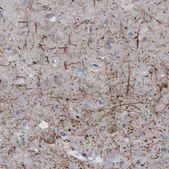

The Human Protein Atlas project can be subdivided into three efforts: Human Tissue Atlas, Cancer Atlas, and Human Cell Atlas. The antibodies that have been generated in support of the Tissue and Cancer Atlas projects have been tested by immunohistochemistry against hundreds of normal and disease tissues and through the recent efforts of the Human Cell Atlas project, many have been characterized by immunofluorescence to map the human proteome not only at the tissue level but now at the subcellular level. These images and the collection of this vast data set can be viewed on the Human Protein Atlas (HPA) site by clicking on the Image Gallery link. We also provide Prestige Antibodies® protocols and other useful information.

• IHC tissue array of 44 normal human tissues and 20 of the most common cancer type tissues.